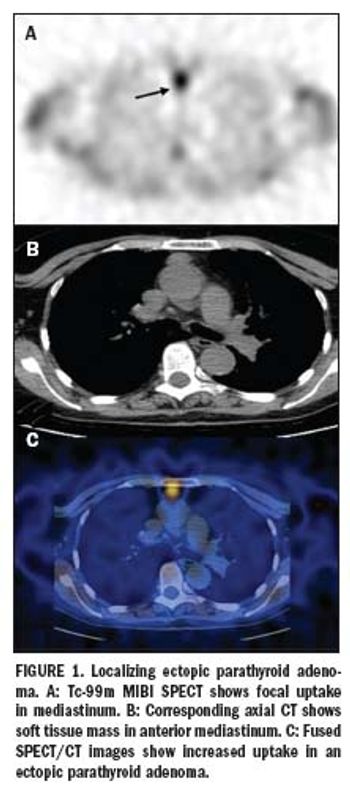

Multislice SPECT/CT gains wider clinical acceptance

ByGopinath Gnanasegaran, MD,Kathryn Adamson, MSc

Multimodality imaging is rapidly becoming an essential tool, particularly in oncology, where many publications have focused on a role for PET/CT.